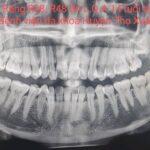

NHỔ RĂNG KHÔN MỌC LỆCH AN TOÀN-KHÔNG ĐAU TẠI BỆNH VIỆN ĐA KHOA HUYỆN...

**Răng khôn hay còn gọi là răng số 8 hay răng cối lớn thứ 3, là răng mọc cuối cùng của hàm. Răng thường...